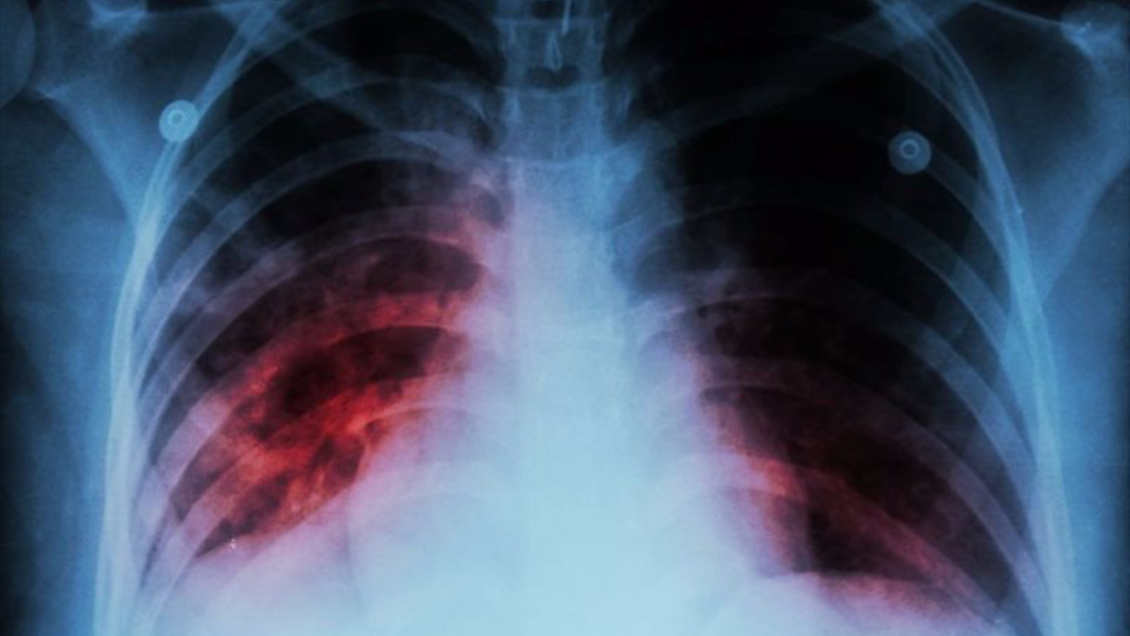

La Seremi de Salud de Valparaíso informó de un caso de tuberculosis pulmonar en un establecimiento educacional de la región, por lo que se activaron todos los protocolos preventivos por este caso.

Sobre los síntomas, la autoridad sanitaria indicó que los más comunes son tos y desgarro por dos semanas o más, el que puede producir sangrado; puede estar acompañado de decaimiento, pérdida de apetito, fiebre, baja de peso y sudores nocturnos.